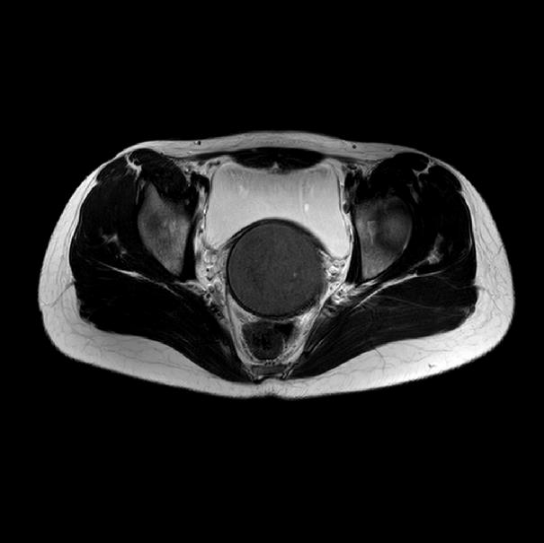

立春这一天,优米app下载ios妇科诊室来了一位特殊的小病号。16岁的花季少女王某突发怪病,腰酸腹痛症状明显,大小便后稍能缓解。最奇怪的是年满16周岁,竟然至今无月经来...